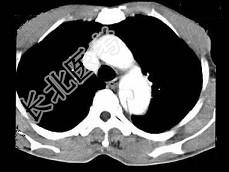

- 单项选择题根据所提供的图像,最可能的诊断是 ( )

A、主动脉瘤

B、主动脉假性动脉瘤

C、主动脉夹层3型

D、主动脉夹2型

E、以上都不是